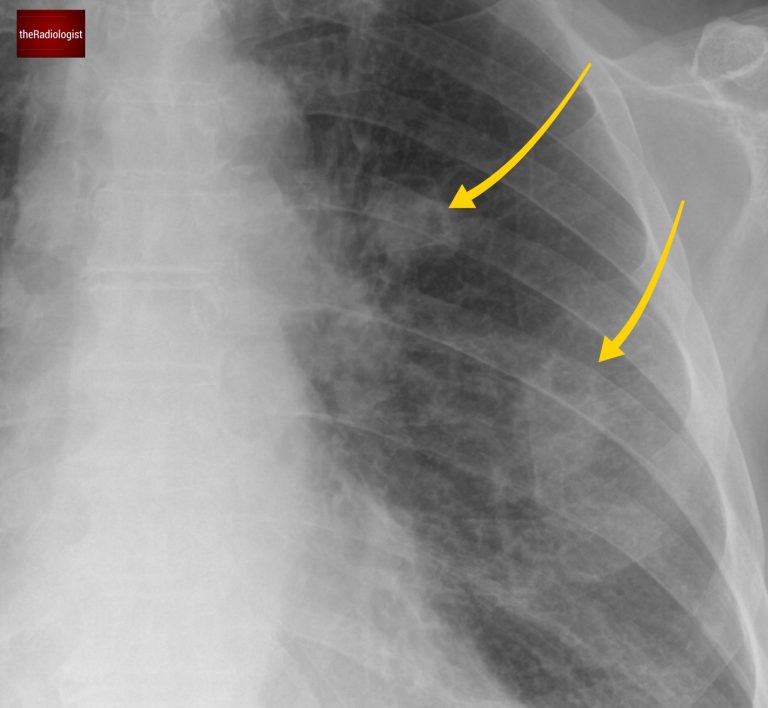

When we zoom in, we can see a bilateral abnormality. On closer inspection, some of these lesions have a small associated lucency, representing gas within the lesion.

Look closely and you will see multiple lung nodules, some of which show internal lucency, ie cavitation

Let’s go back to our case. On closer inspection, the X-ray reveals an abnormal aortopulmonary (AP) window.

• Normally, this area has a concavity, but here it appears full, suggesting mediastinal lymphadenopathy.

• This observation pushes metastatic disease and TB higher up the differential.

Looking at the mediastinum there is filling of the AP window suggesting lymph node enlargement.